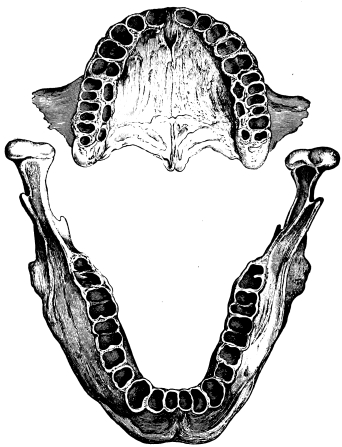

A correct acquaintance with the disposition of the alveoli of the teeth is of importance for skilful and successful operating. Fig. 15 gives a general idea of the appearance of the alveoli, but it is needless to say that a full knowledge can only be really obtained by a careful study of the bones themselves; by this means, too, some idea of the strength of different portions of the alveolar borders can be obtained—a matter of some moment when applying force in the process of removing a tooth from its socket. The points to be specially noted in the maxilla are the thinness of the outer alveolar wall as compared with the inner, the prominence of the canine socket, and the cancellous character of the bone in the region of the third molar. In the mandible the outer alveolar border will be seen to be thinner than the inner, with the exception of that portion in the region of the{13}

third, and often of the second molar; another fact worthy of attention is that at the posterior portion{14} of the socket of the third molar the bone is moderately dense.